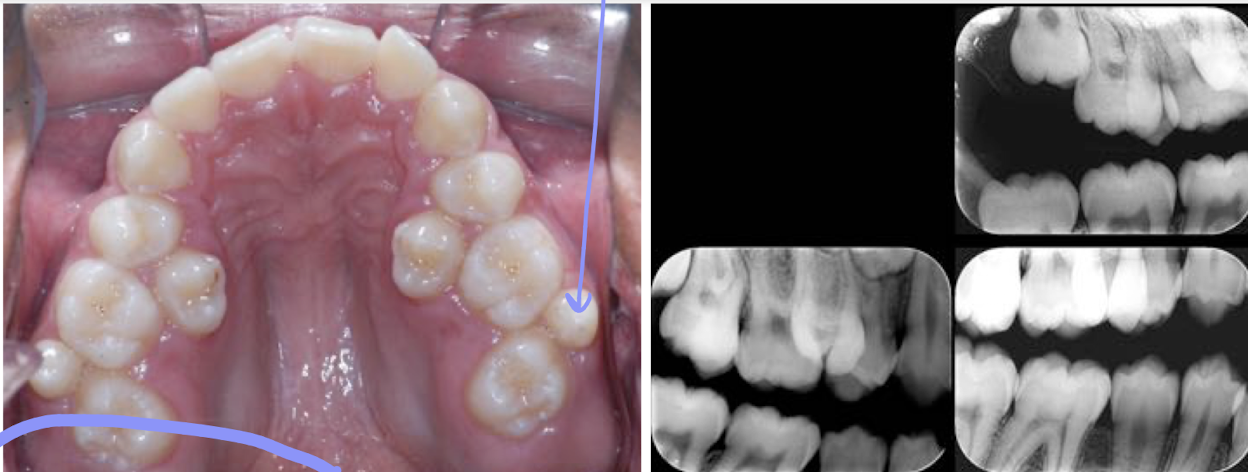

What is the purple line pointing to?

a mesioden